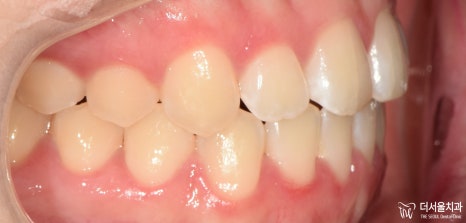

『인비절라인 기간 ’10개월’간의 기록 (치료 마무리)』

다행히 꾸준히 착용을 잘 해주신 덕에

10개월 만에

치료를 마무리할 수 있었습니다.

1) 반대교합 개선

2) 정중선 일치

3) 악궁 (U-shape)

4) 돌출 해소

모든 문제들이 해결이 되었군요.

측면 ceph을 비교해 보면

입술의 긴장감이 사라져

자연스러운 모습으로 바뀌었습니다.